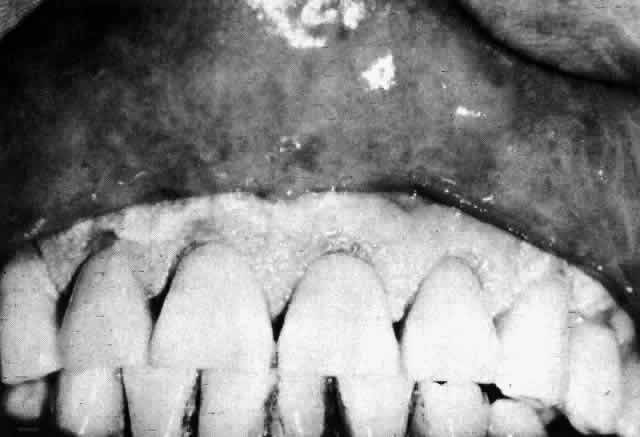

PEMPHIGUS

Pemphigus is a chronic progressive bullous disorder whose several forms depend on clinical morphology (Fig. 10). The most common and well-studied form is pemphigus vulgaris. A variant, pemphigus vegetans, is characterized by vegetative lesions in the intertriginous areas. Pemphigus foliaceus has a high prevalence in Brazil and is characterized by erythematous bullous lesions and generalized exfoliation of the skin in a leaflike pattern. Pemphigus erythematosus has a prolonged erythematous stage and a seborrhea-like eruption.

Fig. 10. Pemphigus vulgaris, Nikolsky's sign. (Courtesy of Dr. JU Dy-Liacco)